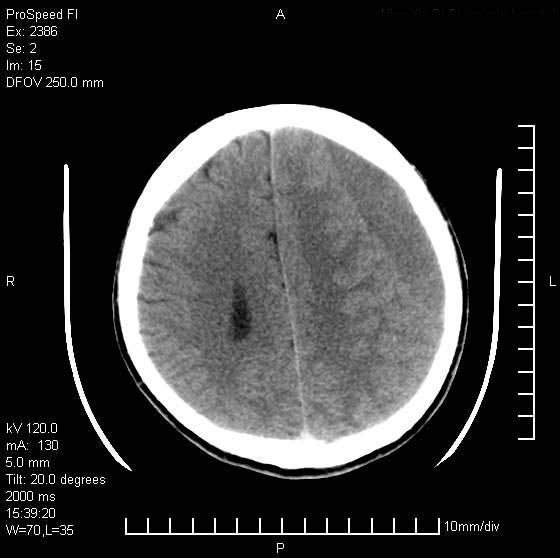

以下是引用天南地北在2007-9-19 18:43:00的发言:[br]典型慢性硬膜外血肿[br][br][本贴已被 天南地北 于 2007-9-19 18:44:11 修改过]

以下是引用曼一拍在2007-9-20 11:06:00的发言:[br]支持慢性硬膜下血肿.[br]慢性硬膜下积液:血肿有包膜,ct值稍高于脑脊液,增强可有染色。不典型者血肿可多呈梭形.是硬脑膜与蛛网膜之间的潜在腔隙内的血肿。[br]鉴别:[br]1\\硬膜外血肿:是颅脑外伤后脑膜或板障内血管破裂,血液在颅骨与硬膜之间积聚所致.通常是脑膜动脉破裂,也可因静脉窦破裂或颅骨的板障静脉出血,发生于外伤的着力部,常与颅骨骨折并存。脑膜动脉出血则急,若是板障静脉出血在则可有慢性。[br]2\\硬膜下积液:(硬膜下水瘤)[br]是由于蛛网膜破裂,脑脊液经蛛网膜破口进入硬膜下腔不能回流。或水肿阻塞而形成。[br]ct表现:颅骨内板下方新月形低密度区近似脑脊液密度;占位效应清,周围无脑水肿。[br]